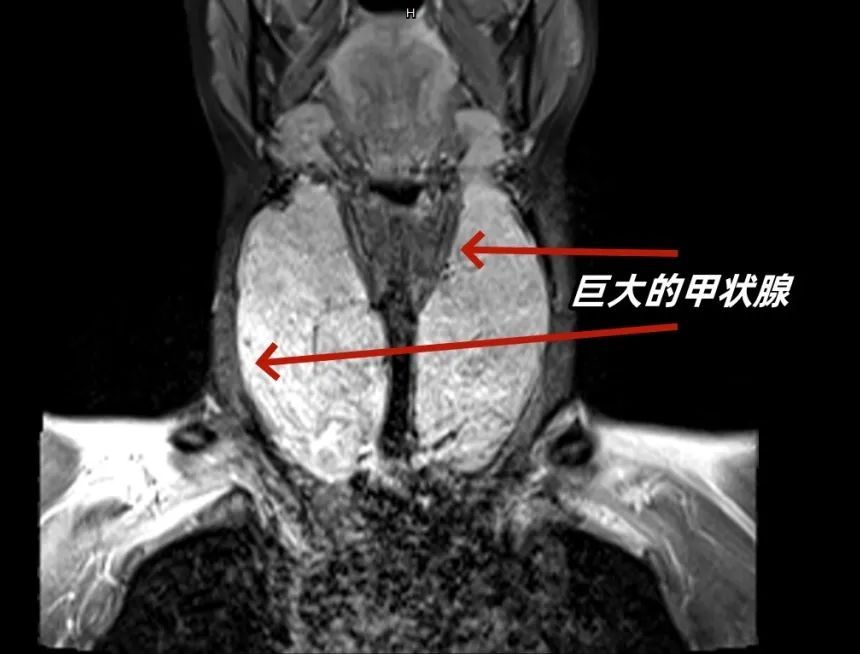

到达急诊时,李女士的情况已十分危急。“患者高热,心率快,血压低。同时,她的甲状腺肿得像一个火龙果,横亘在脖子上,压迫气道,情况危急。”急诊科医生王义辉当即决定给予循环支持、保持气道通畅等措施。

通过多方合作,医生们最终锁定了病因。本着不仅把患者救活,还让患者活得好的原则,还拆除了威胁她生命的“定时炸弹”——巨大的甲状腺。